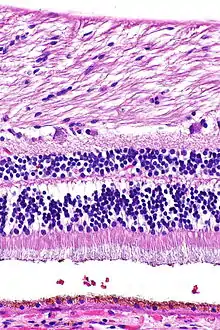

H&E is the combination of two histological stains: hematoxylin and eosin. The hematoxylin stains cell nuclei a purplish blue, and eosin stains the extracellular matrix and cytoplasm pink, with other structures taking on different shades, hues, and combinations of these colors.[5][6] Hence a pathologist can easily differentiate between the nuclear and cytoplasmic parts of a cell, and additionally, the overall patterns of coloration from the stain show the general layout and distribution of cells and provides a general overview of a tissue sample's structure.[7] Thus, pattern recognition, both by expert humans themselves and by software that aids those experts (in digital pathology), provides histologic information.

Hematoxylin principally colors the nuclei of cells blue or dark-purple,[6][15][14] along with a few other tissues, such as keratohyalin granules and calcified material. Eosin stains the cytoplasm and some other structures including extracellular matrix such as collagen[5][7][14] in up to five shades of pink.[8] The eosinophilic (substances that are stained by eosin)[5] structures are generally composed of intracellular or extracellular proteins. The Lewy bodies and Mallory bodies are examples of eosinophilic structures. Most of the cytoplasm is eosinophilic and is rendered pink.[10][15] Red blood cells are stained intensely red.

Ductal carcinoma in situ (DCIS) in breast tissue, cell nuclei (blue-purple), extracellular material (pink). Lung tissue taken from an emphysema patient. Cell nuclei (blue-purple), red blood cells (bright red), other cell bodies and extracellular material (pink), and air spaces (white).

Lung tissue taken from an emphysema patient. Cell nuclei (blue-purple), red blood cells (bright red), other cell bodies and extracellular material (pink), and air spaces (white). Muscle tissue, cell nuclei (blue-purple), cell body (pink).